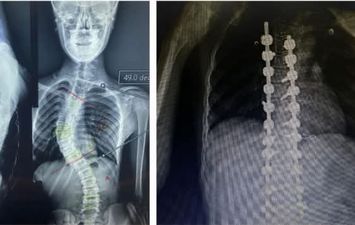

جانب من العملية الجراحية

جانب من العملية الجراحية جانب من العملية الجراحية